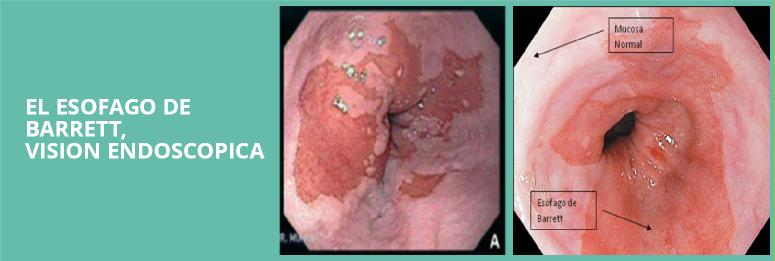

Esófago de Barrett

Considerado como precursor del Cáncer de Esófago, se estima que el 10-20% de los pacientes con reflujo y que se hacen una endoscopia presentan Esófago de Barret, el principal problema esta dado en una sustitución de las células normales del esófago por células intestinales (metaplasia), mas resistentes al acido estas células son las que degeneran en un cáncer (0,5%) cada año

El esófago de barret es mas frecuente en hombres mayores de 55 años que padecen de reflujo mantenido no tratado, de raza blanca y fumadores, no produce síntomas por si mismo si no solo aquellos dependientes del reflujo existente, el diagnostico se establece en pacientes sintomáticos donde al realizar una endoscopia se encuentran cambios en el esófago, la toma de biopsia es imprescindible para dar la certeza al diagnostico